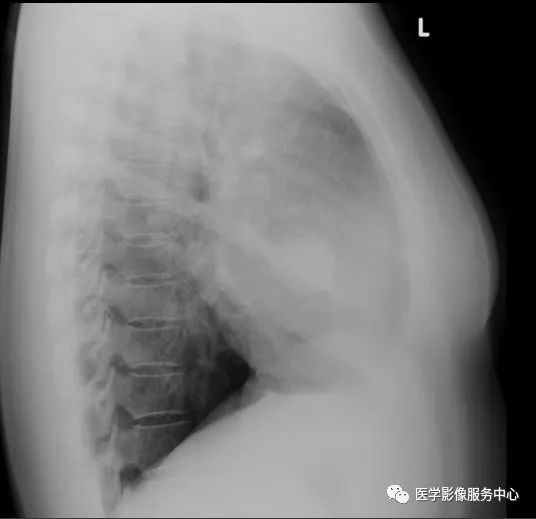

胸片正侧位:右肺中叶见一圆形边界清楚的高密度结节影。 病变中似有“空气新月征”。